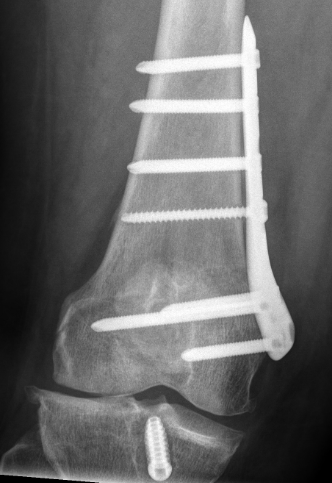

Distal femoral locking plate + bone graft

Medial Closing Wedge Osteotomy

Advantages

- lower risk of non union

- better for larger corrections

Disadvantage

- requires two osteotomy cuts

Distal Femoral Osteotomy MedialDFCO medial closing wedge

Technique

Osteotomy

- insert two K wires for desired wedge

- resect templated wedge

- stop 1 cm short of lateral cortex

- close femoral wedge